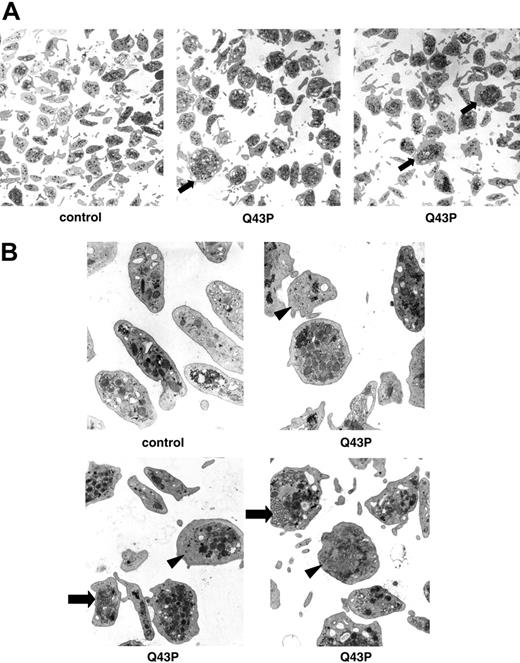

The effect of the Q43P β1-tubulin mutation on platelet morphology

All Q43P β1-tubulin carriers had a normal platelet count, but electron microscopy performed on platelets of 3 Q43P carrier platelets showed the presence of enlarged and rounder platelets compared with the discoid shape of platelets from control subjects (Figure 2A-B), as was also seen in β1-tubulin-deficient mice.7 These abnormal round platelets (about 50% of all platelets) have a disturbed marginal band of microtubules and present with organelle-free zones, centralized platelet granules, and sometimes abnormal membrane complexes.

Ultrastructural analysis of platelets. (A) Electron microscopy of platelets (original magnification, × 7800) of a healthy individual and 2 heterozygous β1-tubulin Q43P carriers (carriers 1 and 2). Almost 50% of Q43P carrier platelets are enlarged and round (arrow). (B) Electron microscopy of platelets (original magnification, × 22 500) of a healthy individual and 3 heterozygous β1-tubulin Q43P carriers, showing cytoplasmic inclusions composed of smooth endoplasmic reticulum and abnormal membrane complexes (arrow). Note also the organelle-free zones in some platelets (arrowhead). There is a normal number of more centralized platelet alpha and dense granules.